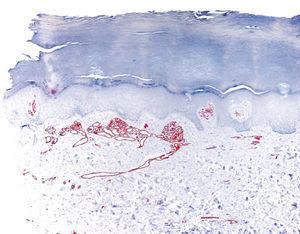

Realizamos una biopsia de la lesión y en el estudio histopatológico destacaba, bajo una epidermis conservada, una proliferación de vasos capilares agrupados en ovillos, con estroma laxo, localizados en las papilas dérmicas (figs. 2 y 3). En el resto de la dermis no existía infiltrado linfocitario ni ningún otro hallazgo patológico. La inmunotinción con CD 31 resultó positiva para las células endoteliales (figs. 4 y 5).

Figura 4. Detalle de la proliferación de vasos capilares. (Inmunotinción CD 31.)

Figura 5. Inmunotinción CD 31 positiva para las células endoteliales.